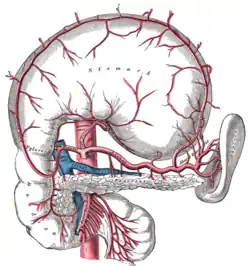

Branches of the celiac artery. (Lienal artery is an old term for splenic artery, and is visible at center. The spleen is at center right. The stomach has been flipped out to reveal the splenic artery, so the greater curvature is at the top in this diagram.) | |

The splenic artery, the largest branch of the celiac trunk, gives off branches to the stomach and pancreas before reaching the spleen.

| Branch | Description |

| branches to the pancreas | multiple branches serving the pancreas including greater pancreatic artery and dorsal pancreatic artery. |

| short gastric | upper part of greater curvature of the stomach and fundus of the stomach |

| left gastroepiploic | middle of greater curvature of the stomach |

| posterior gastric | posterior of stomach, gastric region superior to the splenic artery |

Note that the branches of the splenic artery do not reach all the way to the lower part of the greater curvature of the stomach. Instead, that region is supplied by the right gastroepiploic artery, a branch of the gastroduodenal artery. The two gastroepiploic arteries anastomose with each other at that point.